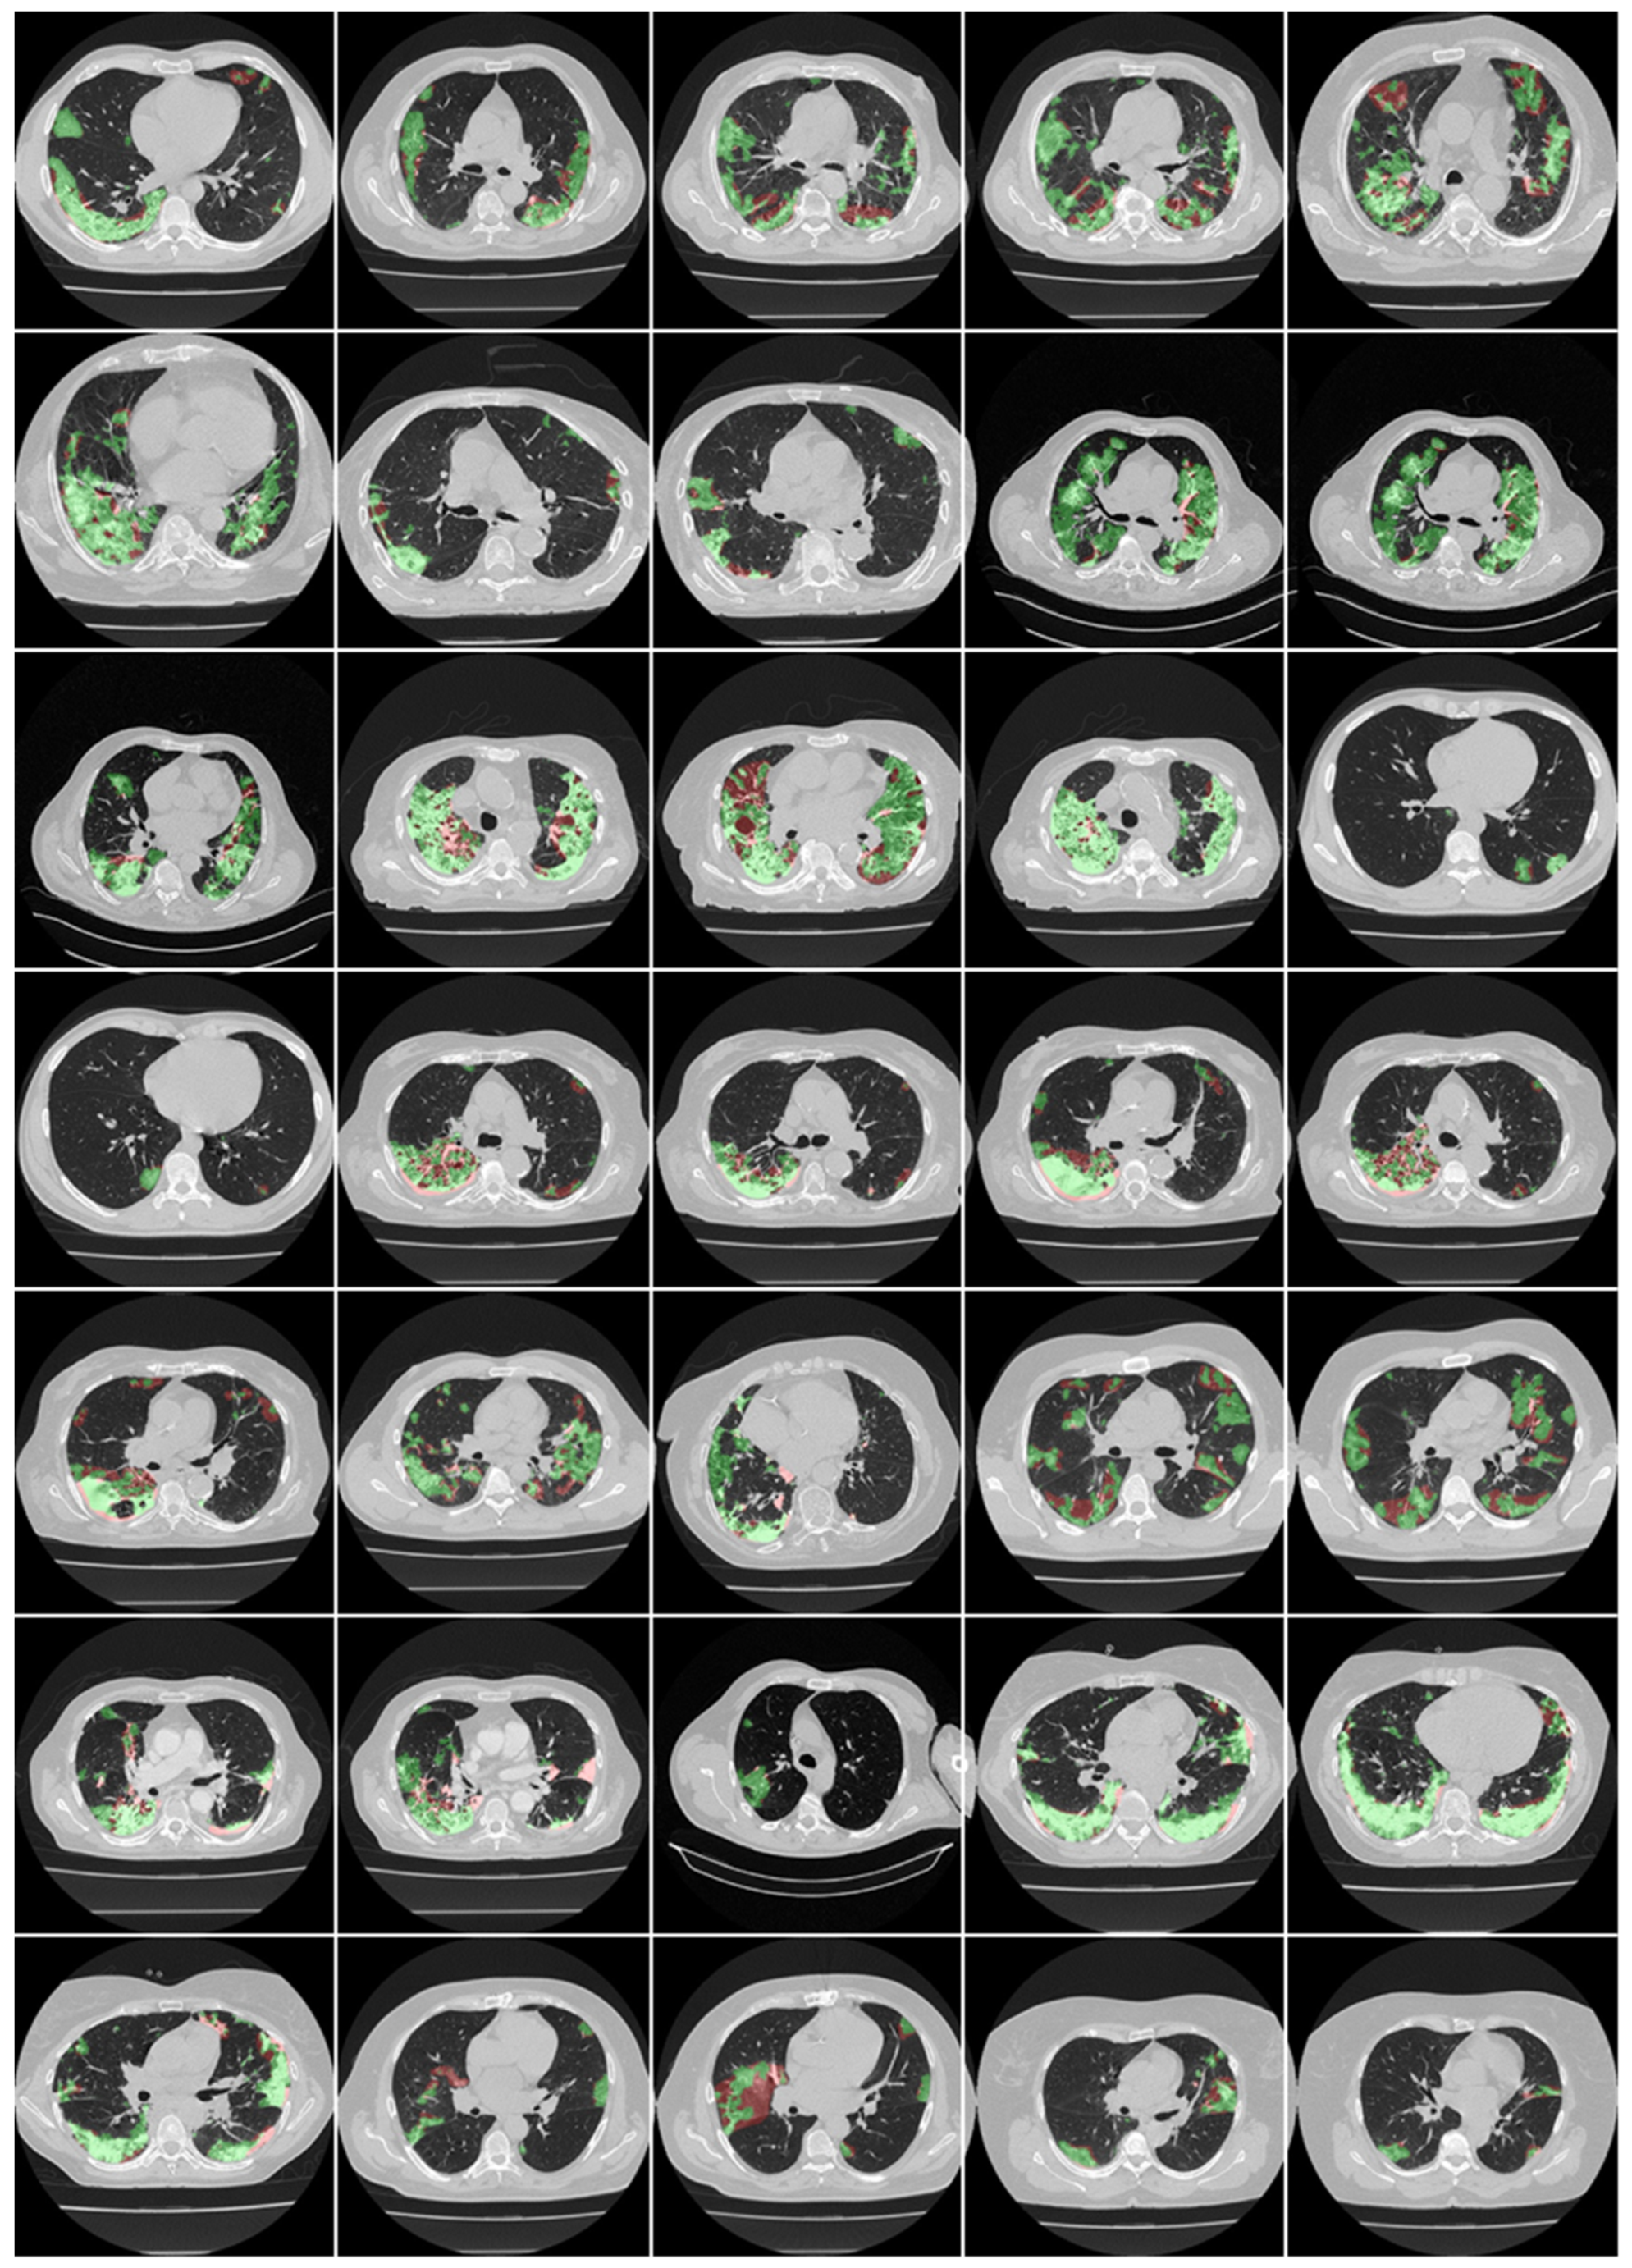

3.1. Results

3.2. Performance Evaluation